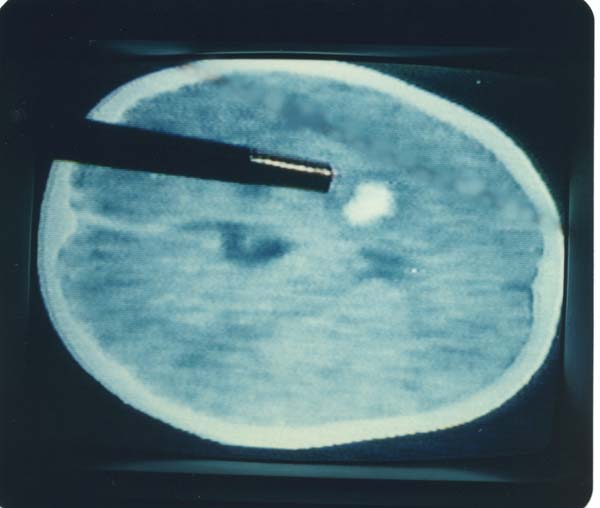

*  A large hemorrhage focus in Hubert's brain.